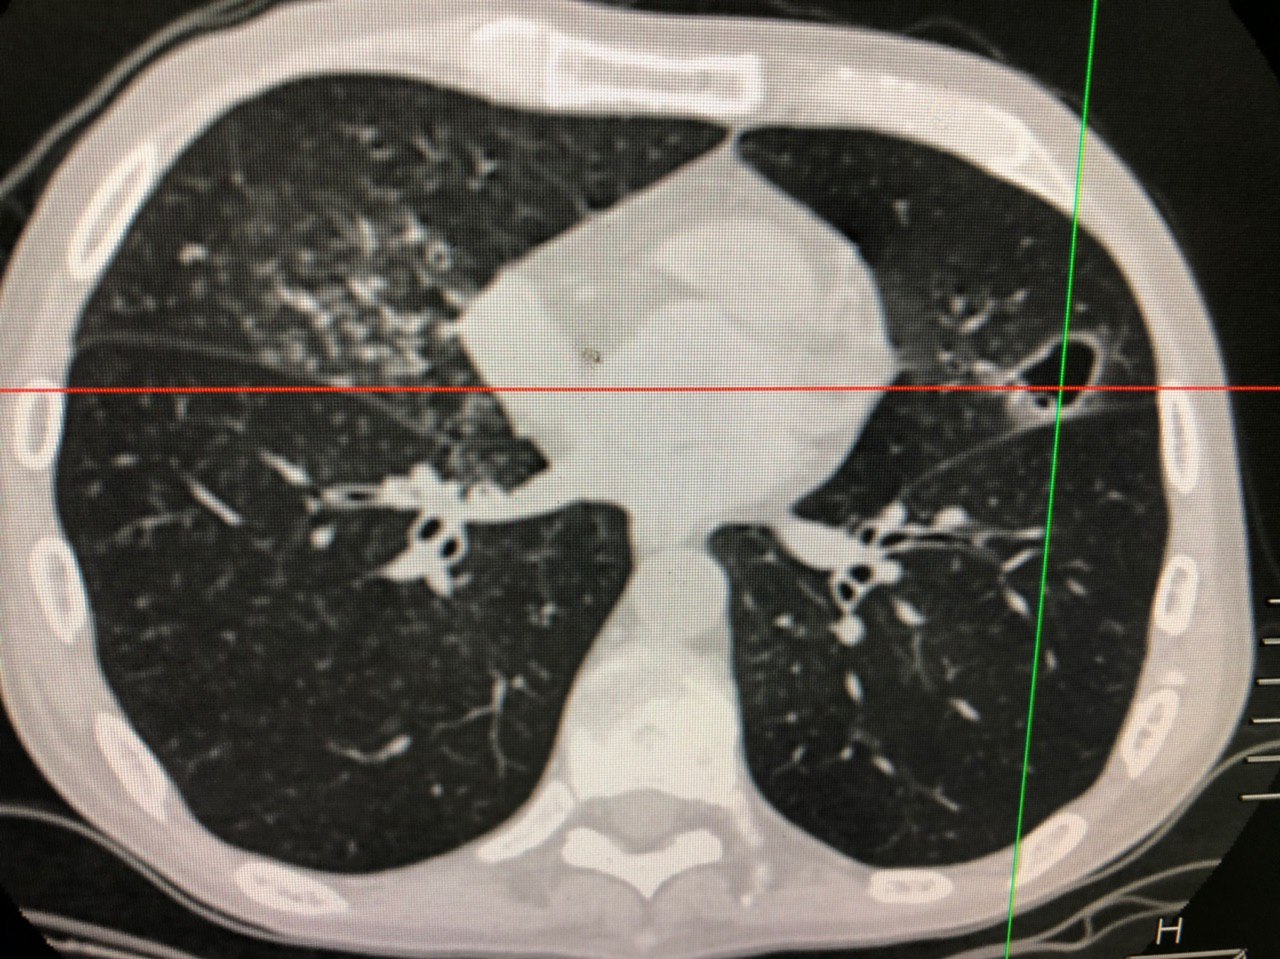

Сутки. Роды в срок. Околоплодные воды зеленые. Т 36,6, лейкоцитоз нарастает. Неонатологи хотят исключить пневмонию

Обещанный кейс

Первый снимок от 05.08.19, второй 15.08.19 на воне а/б терапии

8 лет

На рентгене левая сторона смотрелась не так страшно)

С бронхогенным отсевом в контрлатеральную сторону получается? Что там по БК?